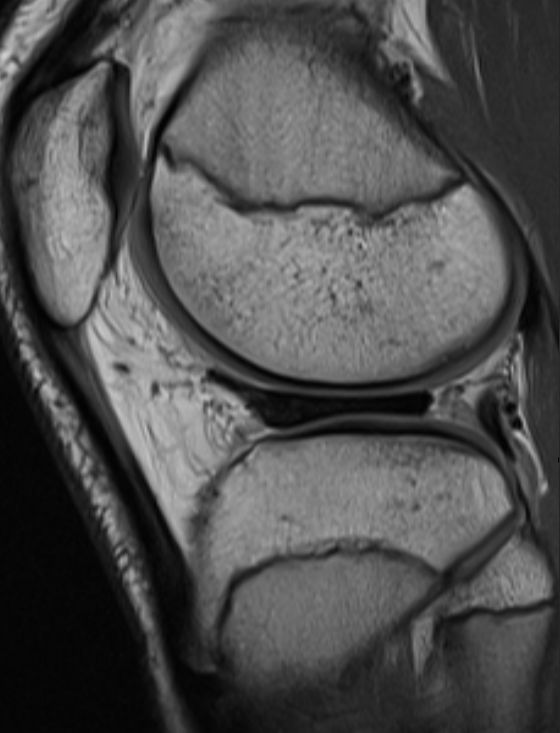

3. Meniscocapsular separation